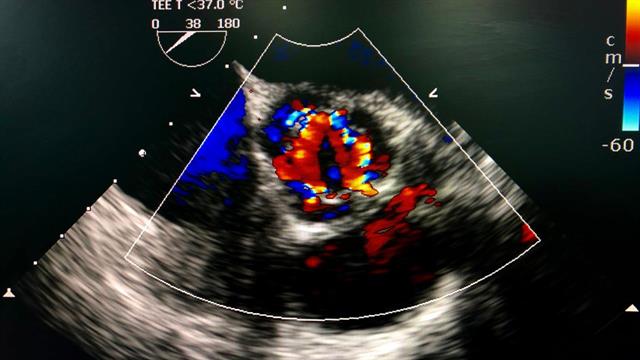

Και στη χώρα μας, η εφαρμογή της επεκτείνεται ικανοποιητικά, υπολείπεται όμως κατά πολύ των χωρών της δυτικής, κεντρικής και πολλών της ανατολικής Ευρώπης, όπως και της Κύπρου. Από άποψη σχεδιασμού υπάρχουν δύο είδη διαδερμικών βαλβίδων αορτής σήμερα, αυτές που διατείνονται με μπαλόνι και αυτές που έχουν ιδιότητες ελάσματος και αυτοεκπτύσσονται, και αναλόγως των κλινικών και ανατομικών χαρακτηριστικών του κάθε ασθενή προκρίνεται η πιο κατάλληλη.

Η ταχεία ανάπτυξη και εξάπλωση διαδερμικών θεραπειών και για τις υπόλοιπες καρδιακές βαλβίδες είναι γεγονός. Πέραν των κλιπς (clips) για τη μιτροειδή και την τριγλώχινα βαλβίδα υπάρχουν και χρησιμοποιούμε πλέον και διαδερμικές βαλβίδες για την πλήρη αντικατάσταση και αυτών των βαλβίδων.  Η μακροχρόνια όμως εμπειρία της διαδερμικής αντικατάστασης της αορτικής βαλβίδας με εξαντλητικά λεπτομερείς και συνεχείς αξιολογήσεις είναι απαράμιλλη και έχει οδηγήσει σε τέτοιο βαθμό εμπιστοσύνης που μας οδηγεί να τη συστήνουμε στην πλειοψηφία των ασθενών.